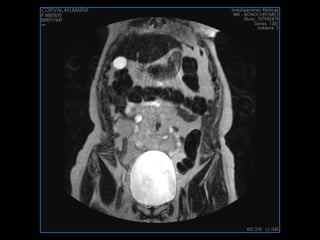

PROTOCOLO pelvis SAG T2, Y FAT SAT (FINOS) AXIAL T1  AX FAT SAT CON   GADOLINIO :  AX T1 Y COR T1 SAT: NO  FASE: RL THK: 3MM  COIL:  GAP: (FACTOR 1.4) 1MM FOV: 40 CM NEX:2 SINCRONIZACION RESPIRATORIA EN 3 O 4 CICLOS ALE